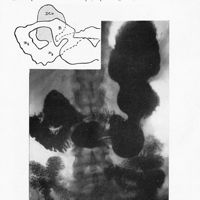

0189 - Page 183 - Séance du 27 janvier 1932. Communications. Note sur l’emploi de la prothèse élastique perdue dans les paralysies musculaires, par M. Albin Lambotte / Image radio graphique d’une grosse pyo-physométrie par cancer végétant de l'isthme, par M. Caraven0189 - Page 183 - Séance du 27 janvier 1932. Communications. Note sur l’emploi de la prothèse élastique perdue dans les paralysies musculaires, par M. Albin Lambotte / Image radio graphique d’une grosse pyo-physométrie par cancer végétant de l'isthme, par M. Caraven

0193 - Page 187 - Séance du 27 janvier 1932. Communications. Image radio graphique d’une grosse pyo-physométrie par cancer végétant de l'isthme, par M. Caraven / Nouvelle observation de « carpe bossu », par MM. J. Fiolle et Ailland0193 - Page 187 - Séance du 27 janvier 1932. Communications. Image radio graphique d’une grosse pyo-physométrie par cancer végétant de l'isthme, par M. Caraven / Nouvelle observation de « carpe bossu », par MM. J. Fiolle et Ailland